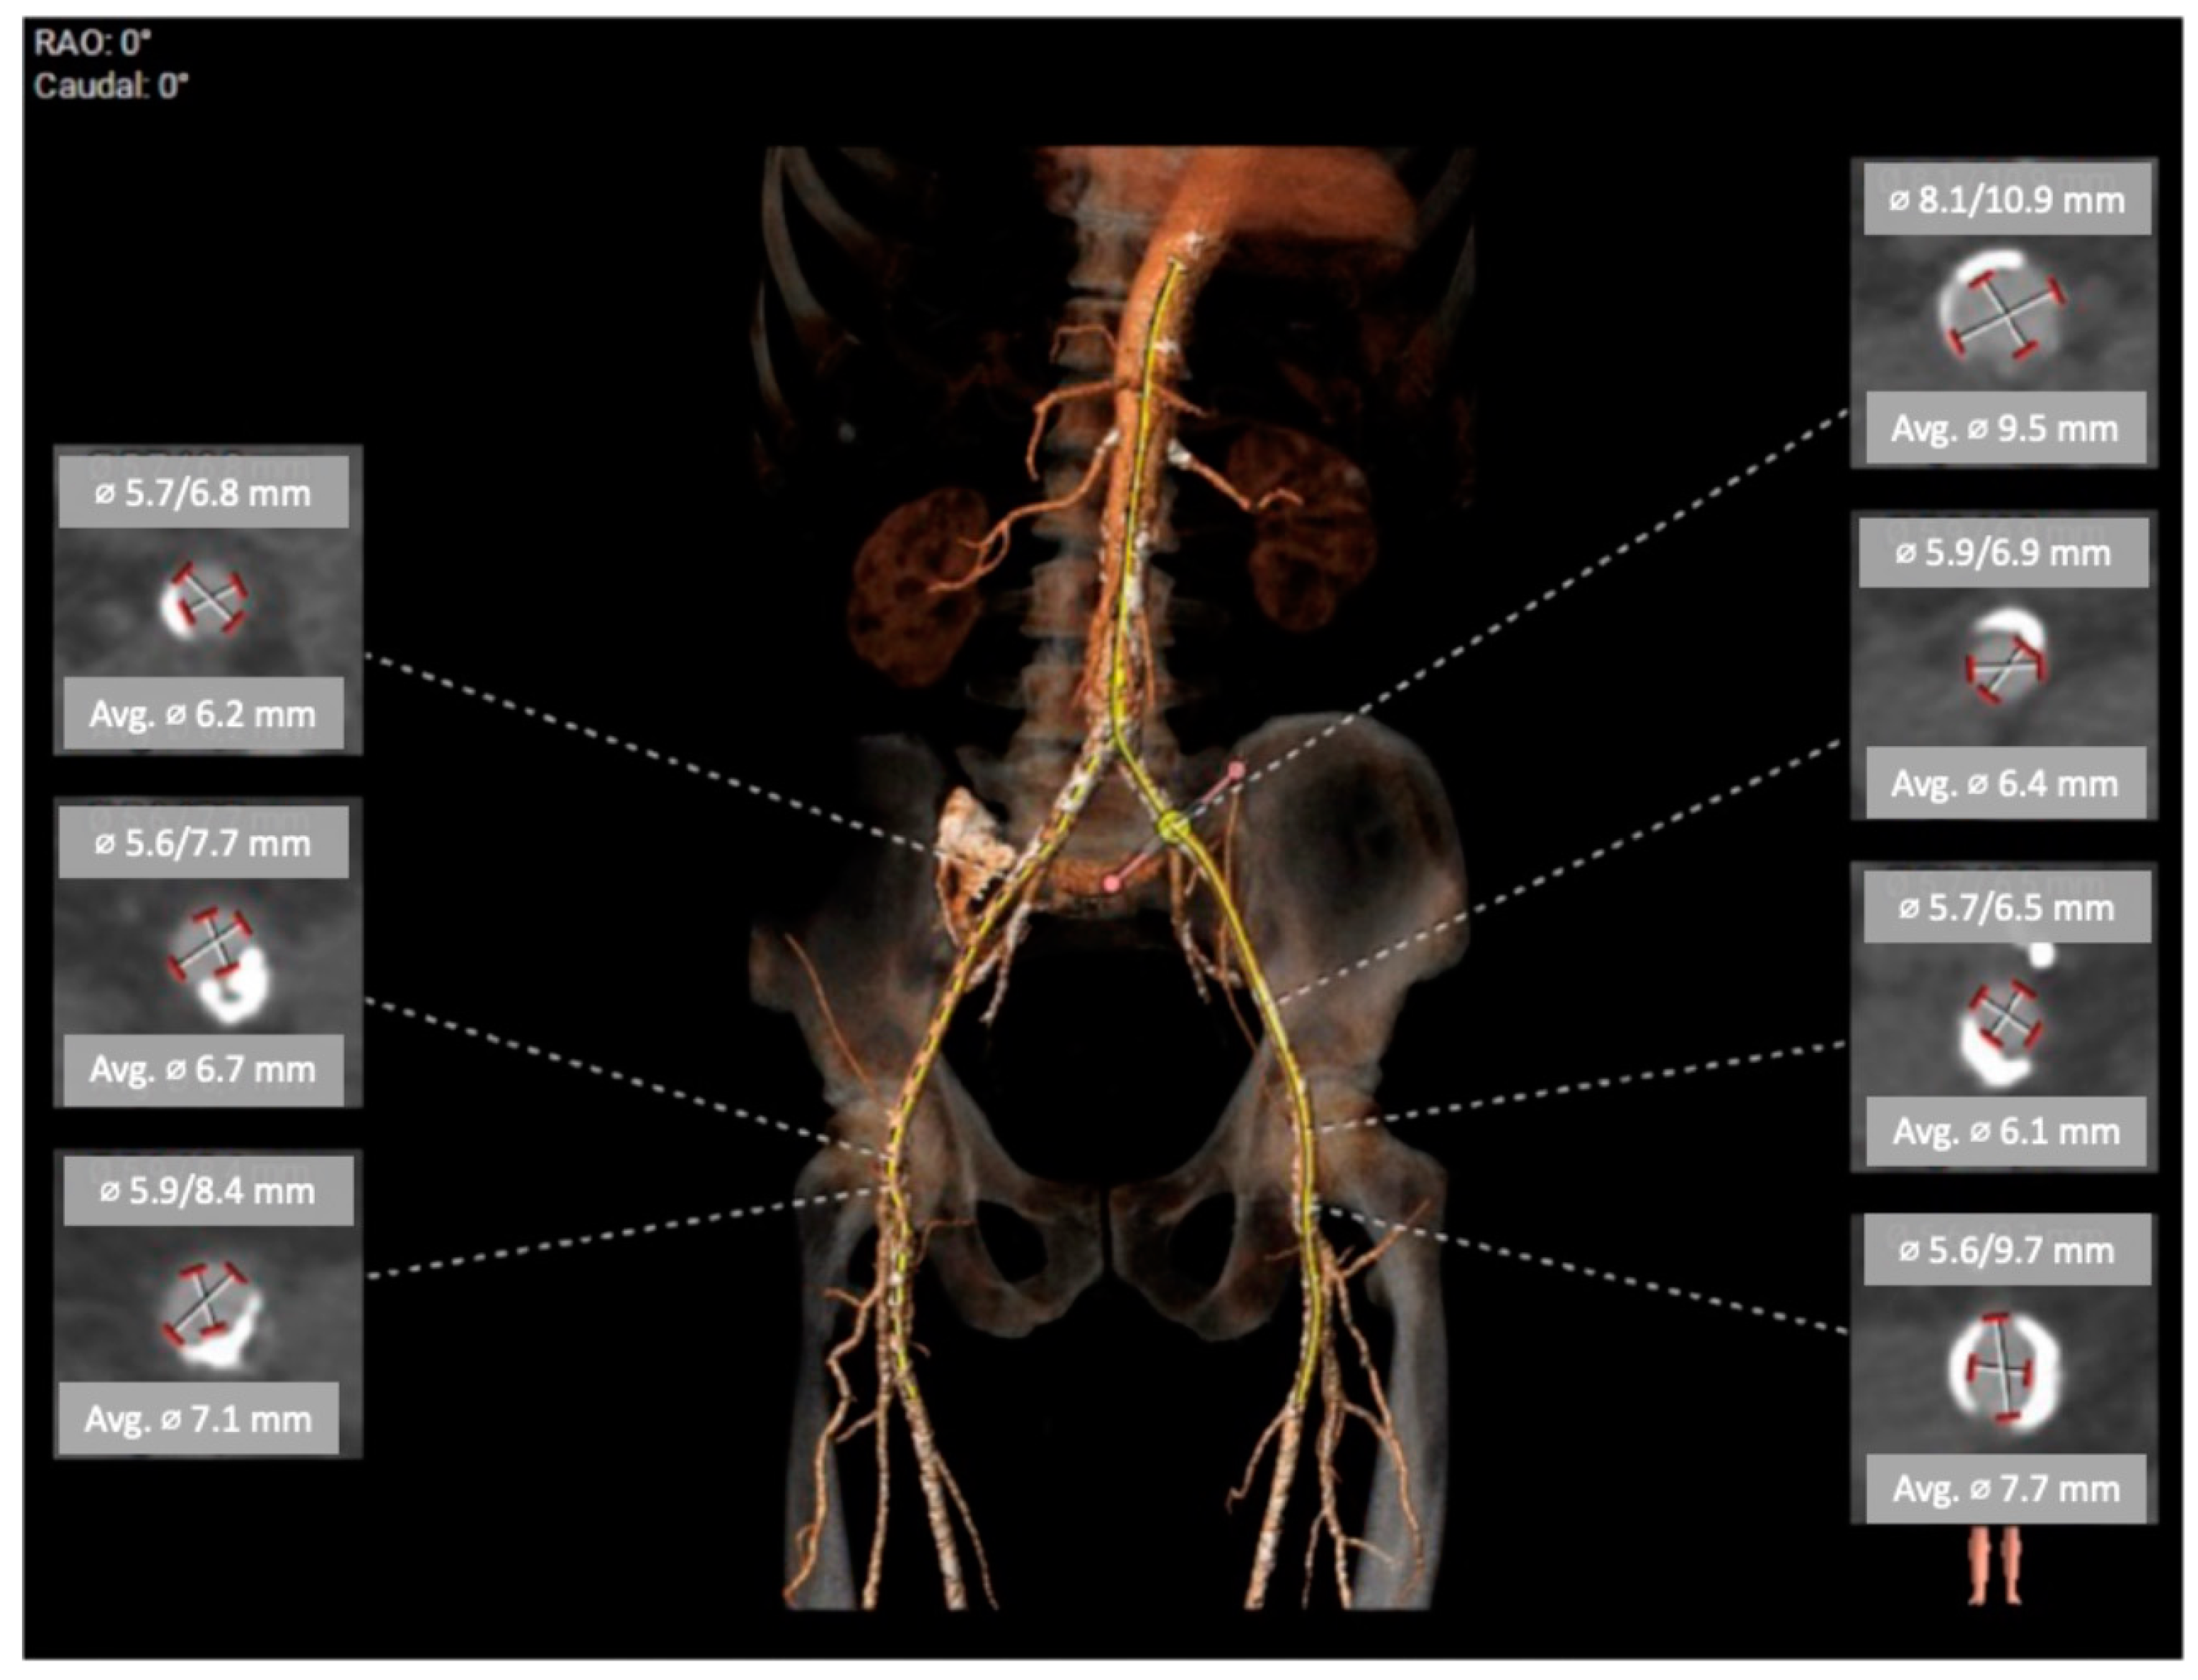

The CTA scan revealed a tricuspid aortic valve with an annulus area of 434 mm2 and dimensions near the lower limit, measuring between 26 mm and 23 mm. Notably, calcium protrusions toward the left ventricular outflow tract (LVOT) were observed below the left coronary cusp (LCC) and non-coronary cusp (NCC), increasing the risk of disturbances. To determine sizing and assess calcium behavior, a balloon valvuloplasty was considered. The left coronary artery (LCA) was found to be at a distance of 15 mm from the aortic annulus, while the right coronary artery (RCA) was at a distance of 17.5 mm. The access vessels showed calcification, with borderline diameters for eSheath placement on both sides. CTA with 3D reconstruction—access vessels is presented in Figure 1. In Figure 2 can be observed aortography of aortic root and ascending aorta, and origins of coronary arteries (a) and CTA 3D reconstruction of aortic root with coronary arteries origin, ascending aorta (b). The lines in Figure 2a represent the plane of the aortic annulus (pink) and the position perpendicular to the aortic axis (yellow). Proper alignment for prosthesis implantation

Figure 1. CTA with 3D reconstruction—access vessels.